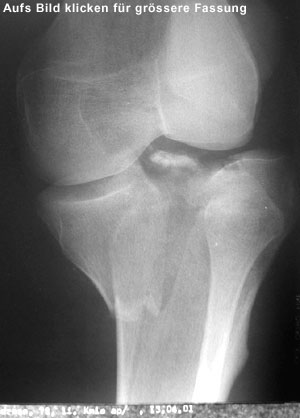

Aber eben, da gabs ja noch was zu operieren - mein Knie war ein ziemliches Mus aus Bänderüberresten, abgebrochenen und tiefergelegten Knochen, dazu noch ein riesiger Bluterguss, daher wartete man bis zum 16. April mit dem Eingriff.

Auf dem Computertomogramm (3D-Rekonstruktion des Schienbeinkopfes bzw. Tibiaplateaus) sieht man schön die Bruchstelle des grossen Knochenfragmentes. Dummerweise geht der Bruch mitten durch die Kniegelenkfläche. Dazu kam noch ein sogenannter Impressionsbruch, hier nur für Profis erkennbar: Ein Teil der Gelenkfläche wurde durch die Gewalt des Sturzes in den Knochen hineingepresst.